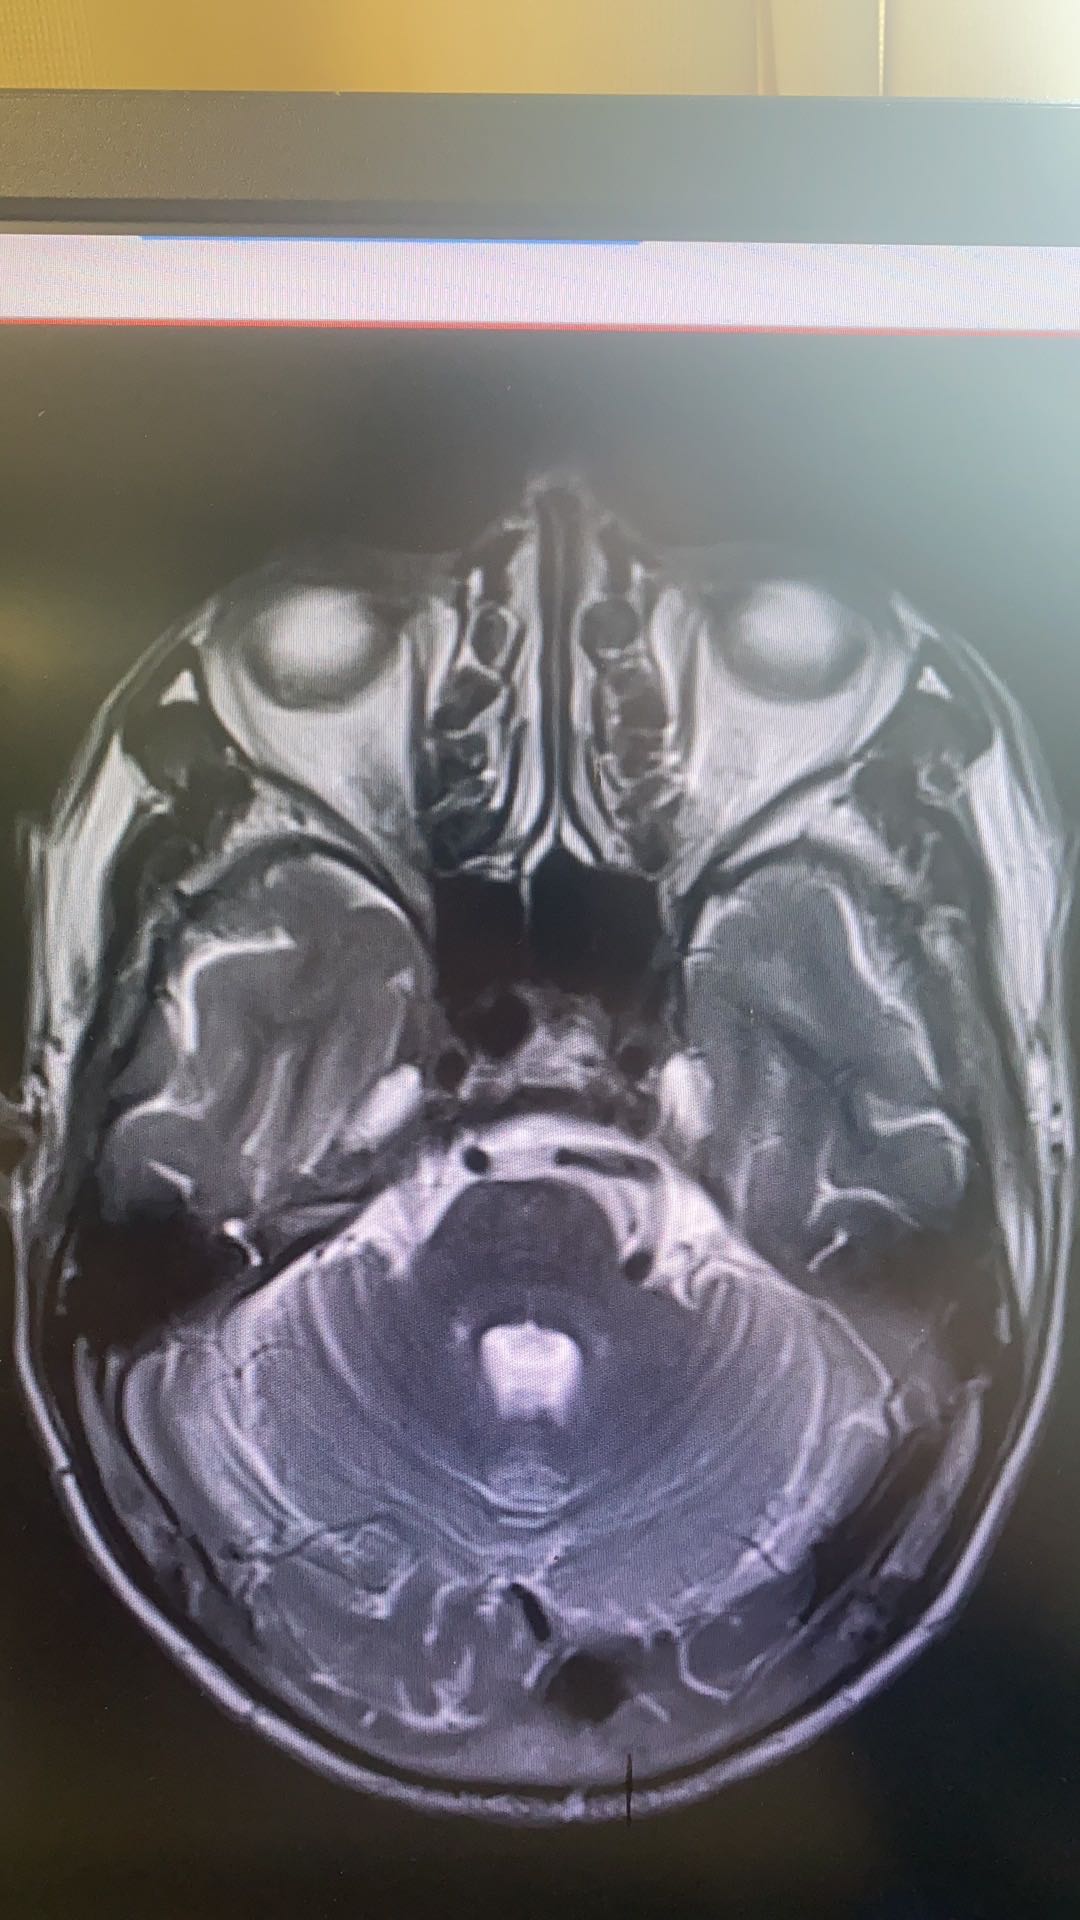

回顾今年8月在印江县人民医院下乡时手术病例,男性,62岁,左侧三叉神经痛5年,加重1年,口服卡马西平无效,封闭多次无效,阅片见为“左侧椎动脉优势型,压迫左侧三叉神经”;完善术前准备,行“左侧三叉神经微血管减压术”。

术中发现左侧椎动脉粗大,与左侧三叉神经紧贴,且有蛛网膜粘连带形成。只有一张垫片可用,此情况下选择用人工硬膜制作“脑膜托”悬吊左侧椎动脉,再置入垫片少许预防性垫隔。术后复查头颅CT未见异常,术后至今未再发生三叉神经痛。